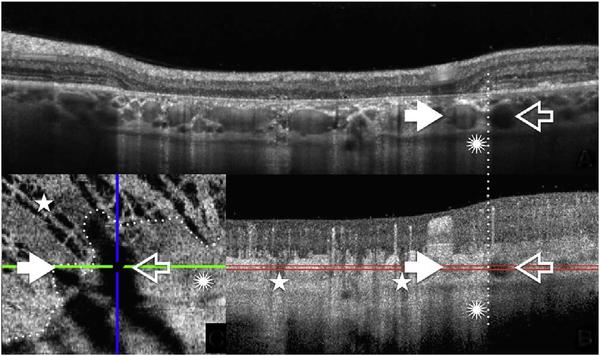

Optical coherence tomography (OCT) was one of the biggest advances in ophthalmic imaging. Building on that platform, OCT angiography (OCTA) provides depth resolved images of blood flow in the retina and choroid with levels of detail far exceeding that obtained with older forms of imaging. This new modality is challenging because of the need for new equipment and processing techniques, current limitations of imaging capability, and rapid advancements in both imaging and in our understanding of the imaging and applicable pathophysiology of the retina and choroid. These factors lead to a steep learning curve, even for those with a working understanding dye-based ocular angiography. All for a method of imaging that is a little more than 10 years old. This review begins with a historical account of the development of OCTA, and the methods used in OCTA, including signal processing, image generation, and display techniques. This forms the basis to understand what OCTA images show as well as how image artifacts arise. The anatomy and imaging of specific vascular layers of the eye are reviewed. The integration of OCTA in multimodal imaging in the evaluation of retinal vascular occlusive diseases, diabetic retinopathy, uveitis, inherited diseases, age-related macular degeneration, and disorders of the optic nerve is presented. OCTA is an exciting, disruptive technology. Its use is rapidly expanding in clinical practice as well as for research into the pathophysiology of diseases of the posterior pole.

光学相干断层扫描(OCT)是眼科成像领域的重大突破之一。在此基础上,OCT 血管造影术(OCTA)提供了视网膜和脉络膜血流的深度分辨图像,其细节水平远远超过了旧的成像方式。这种新的模式具有挑战性,因为需要新的设备和处理技术,目前成像能力的限制,以及成像和对视网膜和脉络膜成像及适用病理生理学的理解的快速发展。这些因素导致学习曲线陡峭,即使对于那些对基于染料的眼部血管造影术有一定了解的人来说也是如此。所有这些都是为了一种成像方法,它的历史还不到 10 年。这篇综述从 OCTA 的发展历史和 OCTA 中使用的方法开始,包括信号处理、图像生成和显示技术。这是理解 OCTA 图像显示内容以及图像伪影产生原因的基础。本文还回顾了眼部特定血管层的解剖结构和成像。介绍了 OCTA 在评估视网膜血管阻塞性疾病、糖尿病性视网膜病变、葡萄膜炎、遗传性疾病、年龄相关性黄斑变性和视神经疾病的多模态成像中的整合。OCTA 是一种令人兴奋的、颠覆性的技术。它在临床实践中的应用以及对后极部疾病病理生理学的研究中迅速扩展。